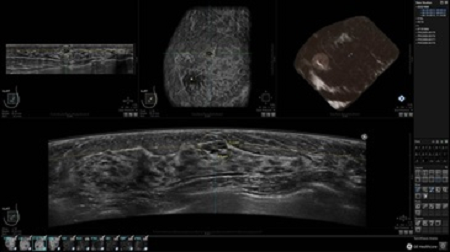

• Получение объемных 3D изображений с возможностью покадрового просмотра

• Алгоритмы обработки изображений: алгоритм однородности изображения ткани (TEA), подавление зернистости, компенсация акустической тени от соска (NSC), определение границ молочной железы (BBD), определение стенки грудной клетки

• Получение изображений в поперечной плоскости (в реальном времени) и в коронарной плоскости (статическая, для указания нахождения соска)

• Отображение объемных 3D ультразвуковых изображений, которые состоят из традиционных поперечных и воссозданных коронарных и сагиттальных проекций

• Возможность отображения полного 3D изображения

• Несколько протоколов для просмотра, которые могут быть настроены пользователем

• Стандартизованная ориентация изображения: «толстый срез» в коронарной плоскости; поперечная; сагиттальная плоскость; радиальный и антирадиальный поворот изображения; просмотр исключительно области интереса

• 360 ° APC - отображение области по «любой точке компаса»